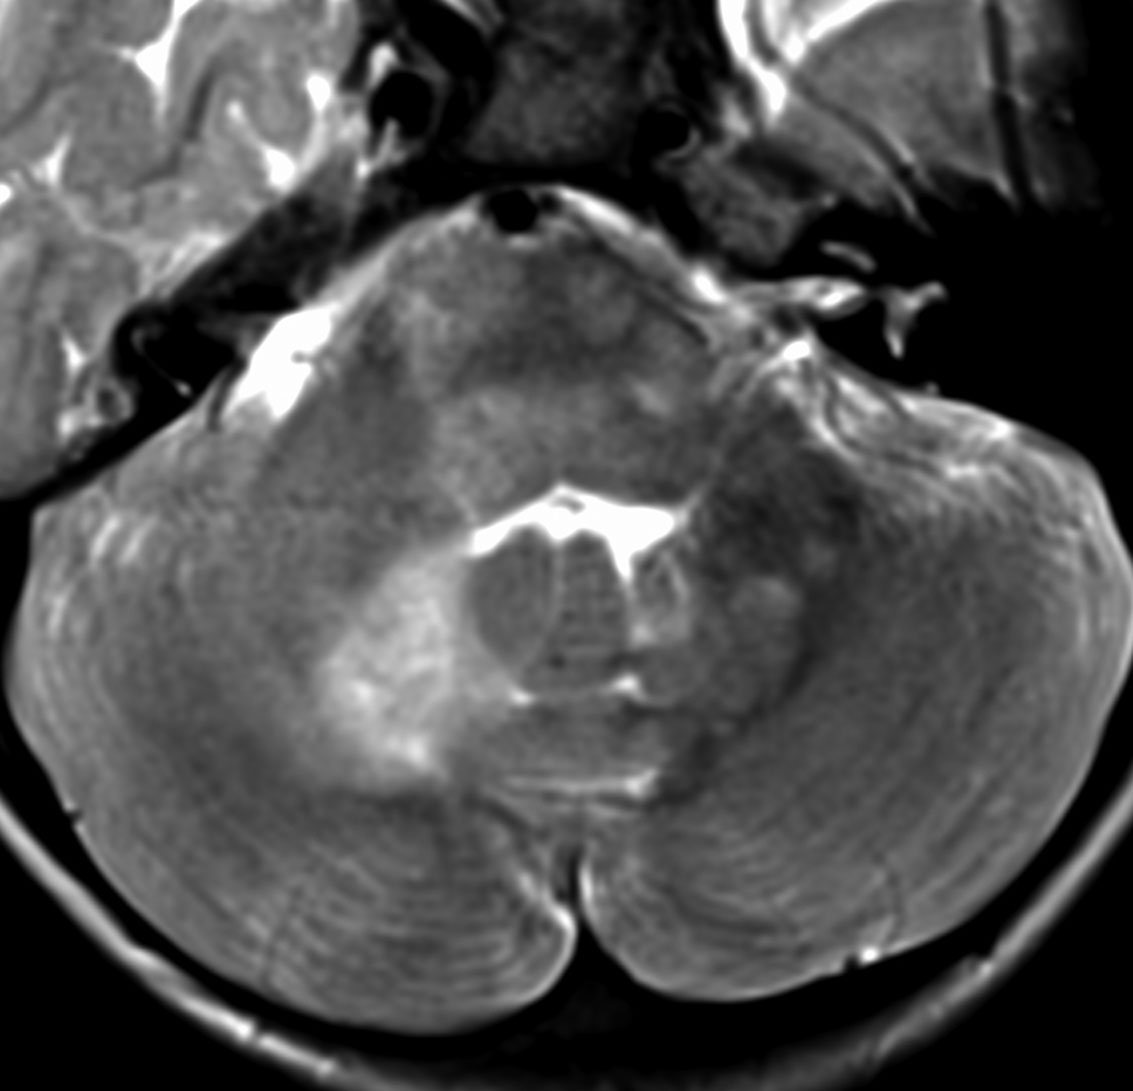

脳幹部グリオーマと間違えそうなもの

3歳の時に,MRIで脳幹部から小脳のグリオーマを疑われて受診しました。橋が腫れて右小脳にもグリオーマのような白い影があります。でもこれは,NF-1のUBOの大きなものです。びまん性正中グリオーマと誤診されて放射線治療を受けてしまった子供もみたことがあります。治療しなくても縮小していくので,何もしないで経過観察します。右側のMRIは13年後のものです。ほとんど消失しています。